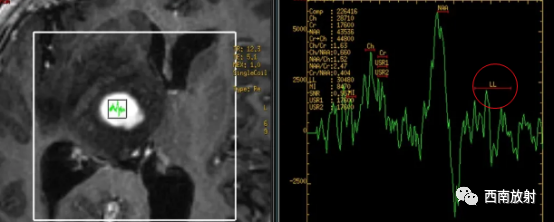

▲病例:脑淋巴瘤。脑深部结节病灶,具有刀切征、凹陷征或肚脐凹征、尖角、多发。DWI呈稍高信号,形态上怪异,波普NAA及Cho减低,出现导致LL峰。颈部、胸廓入口区及腋窝多发淋巴结肿大并相互融合。